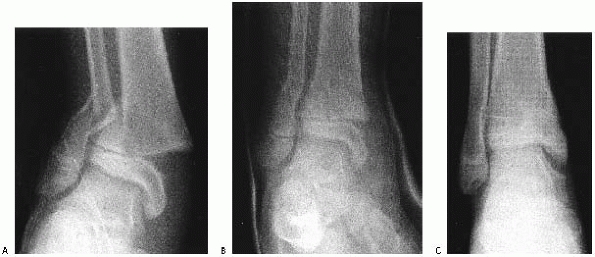

![]() |

FIGURE 26-2

Comminuted Salter-Harris type IV fracture of the distal tibia and displaced Salter-Harris type I fracture of the distal fibula produced by an inversion (shearing) mechanism in a 10-year-old girl. |

fracture of the tibia produced by a shearing (Fig. 26-2)

or crushing force might be more likely to result in growth arrest than